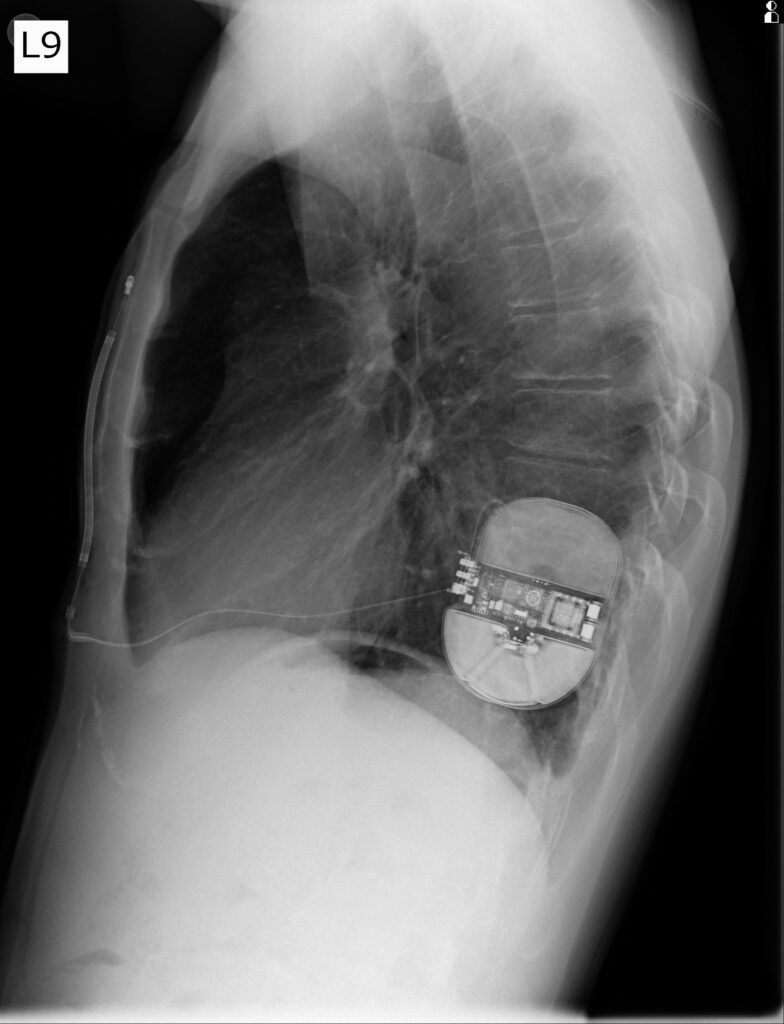

W Pracowni Elektroterapii Kaszubskiego Centrum Chorób Serca i Naczyń w Wejherowie wykonano po raz pierwszy dwa zabiegi implantacji podskórnych kardiowerterów-defibrylatorów (sICD). Są to podskórne urządzenia całkowicie podskórne z elektrodą defibrylacyjną umieszczoną pozanaczyniowo, najczęściej wzdłuż lewego brzegu mostka.

Wspomniane urządzenia nie są dla każdego, co podkreśla dr Roman Moroz, kierownik Pracowni Elektroterapii. Ich wyjątkowość polega na tym, że elektroda defibrylacyjna wszczepiana jest podskórnie, a nie wewnątrzsercowo, jak ma to miejsce w standardowych kardiowerterach-defibrylatorach.

Oba zabiegi wykonano u młodych mężczyzn z ciężkim, przewlekłym uszkodzeniem serca. Trzeba było zabezpieczyć ich na wypadek wystąpienia groźnych dla życia zaburzeń rytmu serca. Jak czytamy na stronie Szpitali Pomorskich, pacjenci po zabiegu czuli się dobrze, a wykonane testy pokazały optymalne położenie urządzenia i elektrody. Ponieważ nie pojawiły się komplikacje, pacjenci wypisani zostali do domu już na drugi dzień.